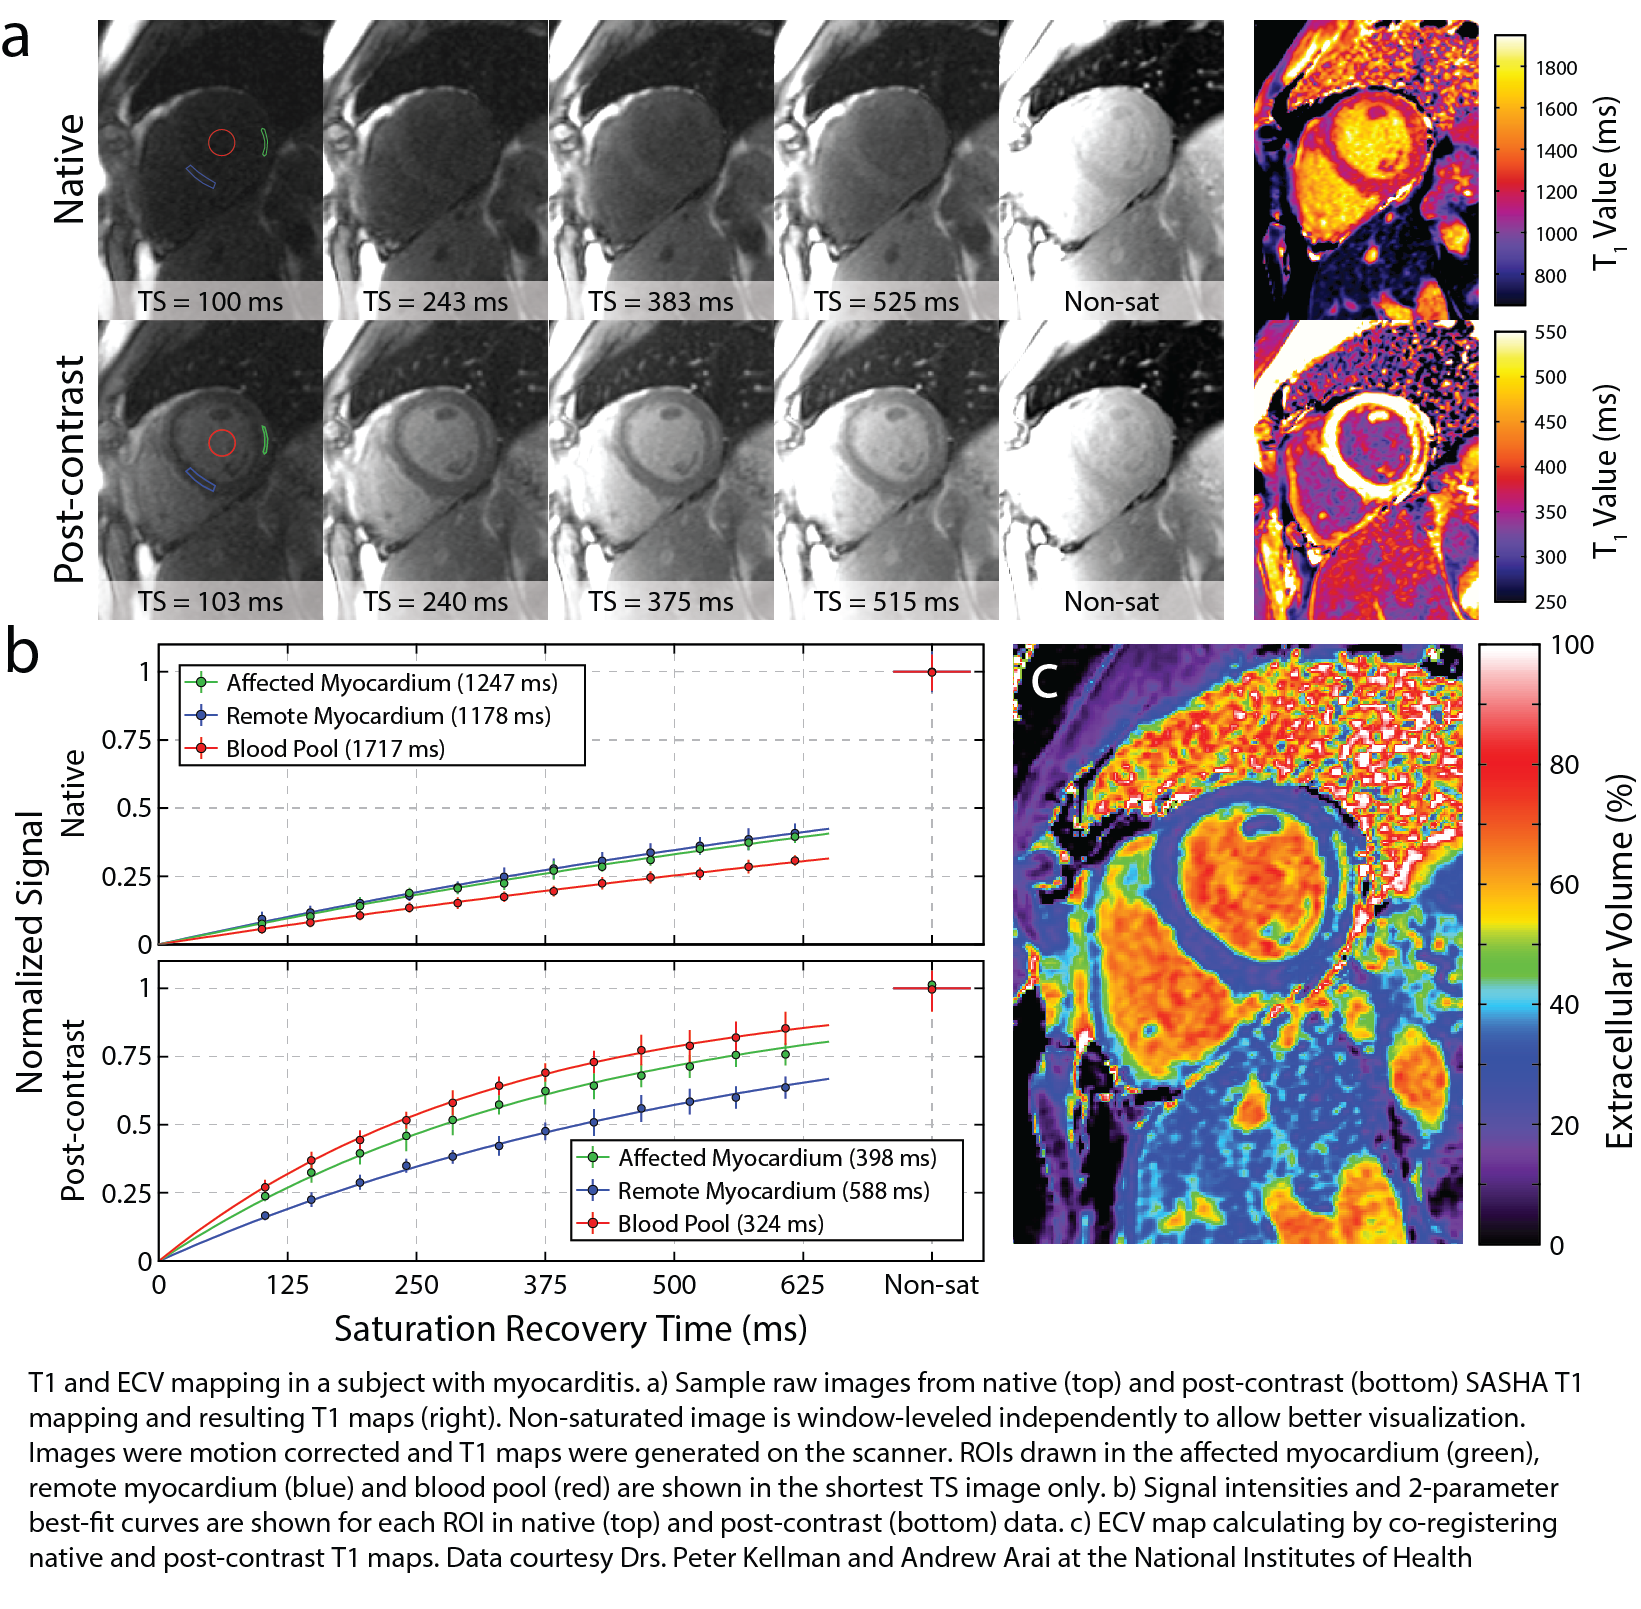

2. Chow, K., Flewitt, J. A., Green, J. D., Pagano, J. J., Friedrich, M. G. and Thompson, R. B. (2014), Saturation recovery single-shot acquisition (SASHA) for myocardial T1 mapping. Magn Reson Med, 71: 2082–2095. doi: 10.1002/mrm.24878

In this work, Kelvin Chow and colleagues proposed a new approach for in vivo cardiac T1 mapping, consisting of a saturation recovery single-shot acquisition (SASHA) with 10 electrocardiogram-triggered single-shot balanced steady-state free precession images acquired in a breath-hold. Their work was validated through Bloch equation simulations, Monte Carlo simulations, and phantom experiments and illustrated in healthy controls and patients with heart failure